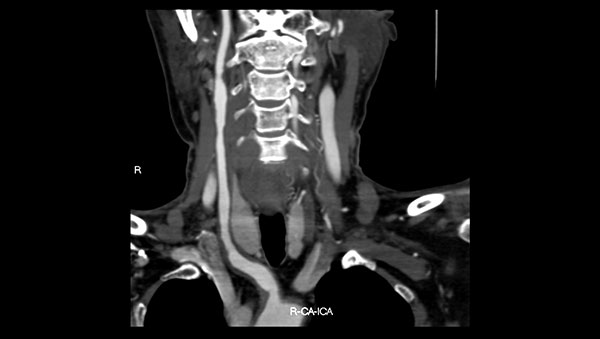

下一篇: 头颈CTA三维重建后